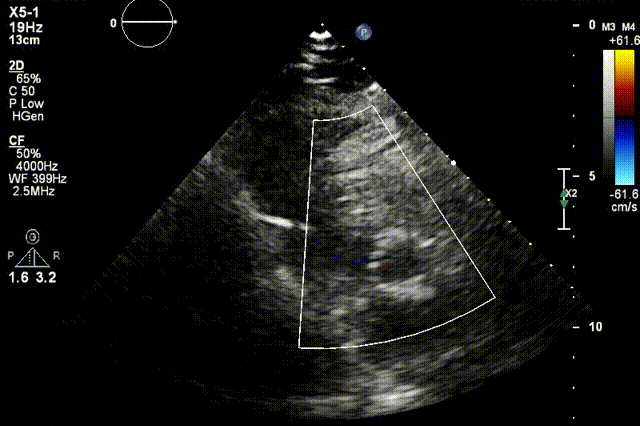

检查结果-术中超声

检查结果-即刻超声

动脉瓣瓣周轻度反流。

经主动脉口收缩期血流最大速度约1.5m/s,最大跨瓣压差约10mmHg。